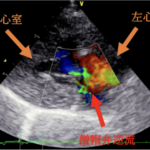

- 猫の肥大型心筋症、拘束型心筋症、動脈血栓塞栓症